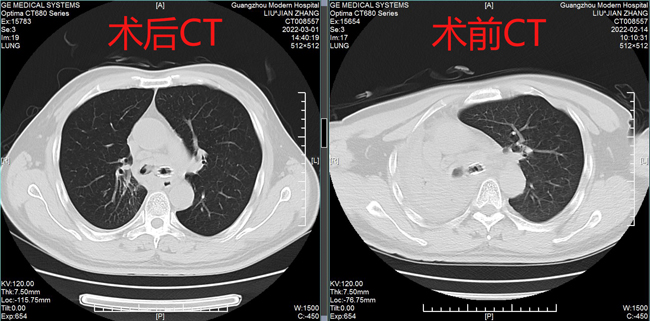

術(shù)前術(shù)后CT表現(xiàn)

據(jù)黃德良主任介紹,劉健患者這次因肺鱗癌引起氣喘問題過來求治的。入院后經(jīng)過完善檢查診斷為右肺鱗癌并胸膜、肺門、縱膈淋巴結(jié)轉(zhuǎn)移,已是T4N2M1屬于肺癌IV期了。“當時情況非常緊迫,患者右主支氣管主干完全堵塞,左主支氣管堵塞,雖然之前在外院做了支架,但支架近端也有腫瘤導致大部分的堵塞。病人呼吸困難,經(jīng)皮血氧低于80%。在麻醉科,氣管鏡室和8樓醫(yī)護共同努力下給病人行右主支氣管腫物微波消融術(shù),術(shù)后氣道恢復通暢,右肺完全復張!患者手術(shù)中還出行反復出血,情況非常不理想,幸得患者家屬無條件的信任,經(jīng)過團隊的共同努力,歷時3個多小時的手術(shù)還是順利完成。目前病人已經(jīng)可以下床走路,經(jīng)皮血氧恢復至95%?!?月15日,經(jīng)過黃教授團隊的評估后,患者接受了介入化療方案,術(shù)后患者呼吸困難癥狀得到進一步改善,指尖血氧好轉(zhuǎn)。在2月20日再次接受氣管鏡下雙側(cè)主支氣管腫物微波消融術(shù)。3月1日復查了CT,患者腫塊縮小,右肺復張。